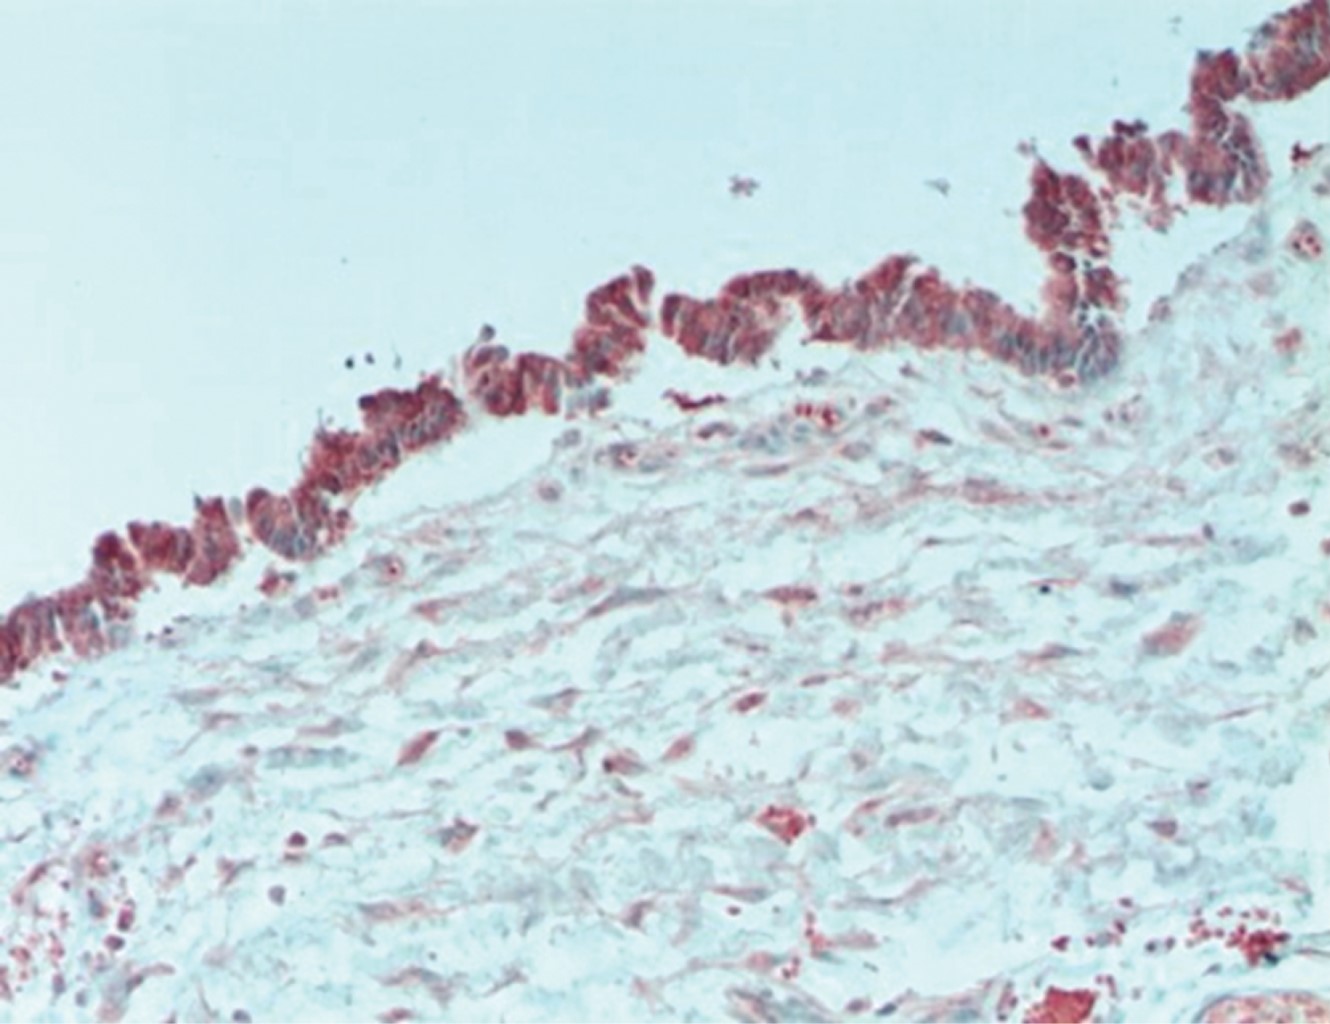

El examen anatomopatológico mostró un quiste multiloculado situado en la dermis profunda (Figura 1), rodeado de tejido conectivo laxo sin músculo liso. A mayor aumento, se observaron cilios finos en el lado luminal del revestimiento epitelial (Figura 2). Las células ciliadas columnares simples mostraron semejanza con el epitelio de Müller. La inmunohistoquímica reveló fuerte positividad citoplasmática para PR (Figura 3) y fuerte positividad intranuclear para ER (Figura 4). El diagnóstico definitivo fue quiste ciliado cutáneo. Sin recidivas durante el seguimiento.

Los hallazgos inmunofenotípicos corresponden a la teoría de la heterotopía del epitelio ciliado del epitelio mülleriano, reactivo para antígenos de pancitoqueratina (CK AE1/AE3), antígeno de membrana epitelial (EMA), receptores de estrógeno (ER), receptores de progesterona (PR), proteína del tumor de Wilms (WT-1) y gen 8 de caja emparejada (PAX-8).7 Se calcula la no reactividad inmunitaria para S100, actina de músculo liso (SMA), antígeno carcinoembrionario (CEA), desmina, factor de transcripción tiroideo (TTF1), p63 y proteína ácida fibrilar glial (GFAP).7 Se ha demostrado que PAX-8, un miembro de la familia de factores de transcripción de caja emparejada (PAX) es importante en el desarrollo de los órganos müllerianos y tiroideos. Se expresa en los núcleos de las células de revestimiento de estos quistes ciliados mediante inmunohistoquímica.4 WT-1, el producto de un gen que es esencial para el desarrollo de los riñones y las gónadas, también es positivo, lo que respalda aún más el origen mülleriano de estos quistes.6